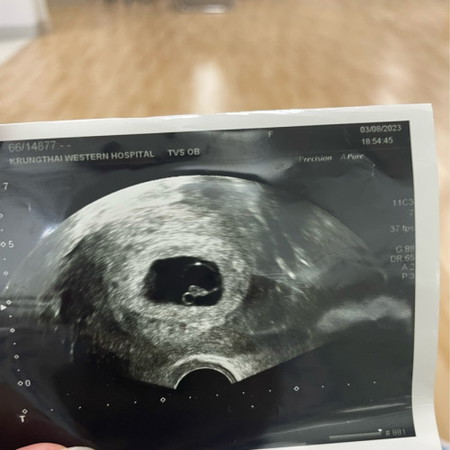

เด็กหยุดการเจริญเติบโต 8week

วีคที่แล้วตรวจยังไม่เจอหัวใจเต้น วีคนี้คุณหมอแจ้งว่าเด็กหยุดการเจริญเติบโต ขนาดเท่าเดิมไม่โตจากวีคที่แล้วเลย ตอนนี้แม่เศร้า เสียใจมากเลยค่ะ วีคหน้าหมอนัดไปยุติการตั้งครรภ์ โดยการอมหรือเหน็บยา มีใครเคยเจอแบบนี้บ้างคะ กลัวมากเลยค่ะ 😰#ท้องแรกคะ #ขอคำแนะนำหน่อยค่ะ